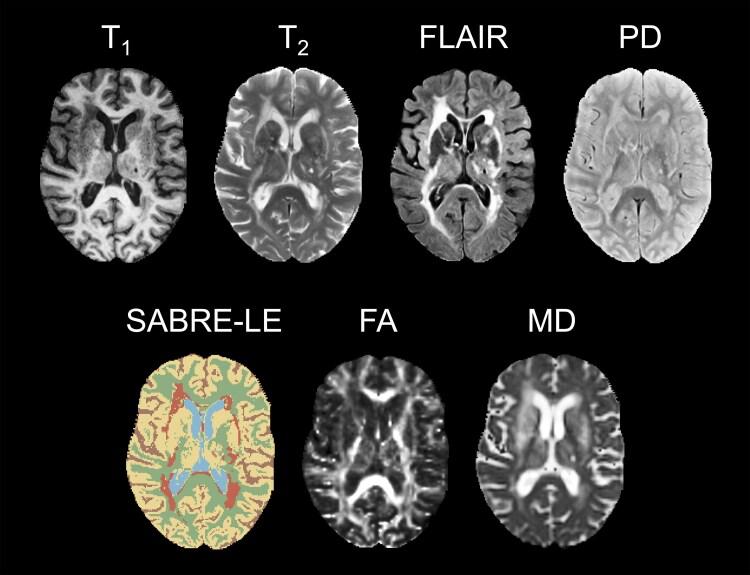

Assessment of spoken language is a promising marker for cognitive impairment in individuals with cerebrovascular disease. However, the underlying neurological basis for spoken language beyond single words and sentences remains poorly defined in this cohort, particularly with respect to white matter. This study aimed to examine and compare white matter hyperintensity volumes and diffusion tensor metrics in normal-appearing white matter (NAWM) as potential correlates of spoken language performance. Baseline imaging and spoken language data were obtained from the cerebrovascular disease cohort of the Ontario Neurodegenerative Disease Research Initiative ( = 127; age: 55-85 years). Most participants had subclinical or very mild strokes, with very little to no aphasia symptoms. Spoken language samples were analysed to compute 10 different measures related to syntax, productivity, lexical diversity, fluency, and information content. Structural and diffusion MRI data were analysed to segment white matter hyperintensities and tracts. Normalized white matter hyperintensity volume, as well as average fractional anisotropy and mean diffusivity in the normal-appearing portion of eight white matter tracts, were correlated with the 10 spoken language measures using canonical correlation analyses. White matter and spoken language variate scores for individual participants then were correlated separately in male ( = 86) and female ( = 41) participants to probe potential sex differences. Spoken language performance was significantly associated with the fractional anisotropy ( = 0.51,   0.041) and mean diffusivity ( = 0.56,   0.011) of NAWM, particularly in the left superior longitudinal fasciculus, but not with white matter hyperintensity volumes ( = 0.41,   0.80) in the same tracts. Measures related to syntax, fluency, and information content loaded most strongly in the spoken language variate. No significant sex differences were found in NAWM microstructure, and female and male participants exhibited similarly strong associations between spoken language and NAWM microstructure (fractional anisotropy: = 1.44, = 0.15; mean diffusivity: = 1.03, = 0.30). These results suggest that diffusion MRI in NAWM may be superior to white matter hyperintensity volumetrics when evaluating the role of white matter tract integrity on cognitive outcomes in people with relatively mild cerebrovascular pathology. These results also demonstrate that multi-domain spoken language analysis is sensitive to underlying white matter microstructure in participants with cerebrovascular disease without significant aphasia, supporting its value as a tool for assessing cognitive status.

对患有脑血管疾病的个体而言,口语评估是认知障碍的一个很有前景的指标。然而,在这一队列中,除了单词和句子之外,口语背后的神经学基础仍未明确界定,尤其是在白质方面。本研究旨在检查和比较正常外观白质(NAWM)中的白质高信号体积和扩散张量指标,作为口语表现的潜在相关因素。基线成像和口语数据来自安大略神经退行性疾病研究倡议的脑血管疾病队列(n = 127;年龄:55 - 85岁)。大多数参与者有亚临床或非常轻微的中风,几乎没有失语症状。对口语样本进行分析,以计算与句法、生成能力、词汇多样性、流畅性和信息内容相关的10种不同测量指标。对结构和扩散MRI数据进行分析,以分割白质高信号和纤维束。使用典型相关分析,将标准化的白质高信号体积以及8条白质纤维束正常外观部分的平均分数各向异性和平均扩散率与10种口语测量指标进行相关性分析。然后分别在男性(n = 86)和女性(n = 41)参与者中,将个体参与者的白质和口语变量分数进行相关性分析,以探究潜在的性别差异。口语表现与NAWM的分数各向异性(r = 0.51,p < 0.041)和平均扩散率(r = 0.56,p < 0.011)显著相关,尤其是在左侧上纵束,但与同一纤维束中的白质高信号体积(r = 0.41,p = 0.80)无关。与句法、流畅性和信息内容相关的测量指标在口语变量中负荷最强。在NAWM微观结构方面未发现显著的性别差异,女性和男性参与者在口语和NAWM微观结构之间表现出同样强烈的关联(分数各向异性:r = 1.44,p = 0.15;平均扩散率:r = 1.03,p = 0.30)。这些结果表明,在评估白质纤维束完整性对患有相对轻度脑血管病变的人的认知结果的作用时,NAWM中的扩散MRI可能优于白质高信号体积测量。这些结果还表明,多领域口语分析对没有明显失语的脑血管疾病参与者的潜在白质微观结构敏感,支持其作为评估认知状态工具的价值。